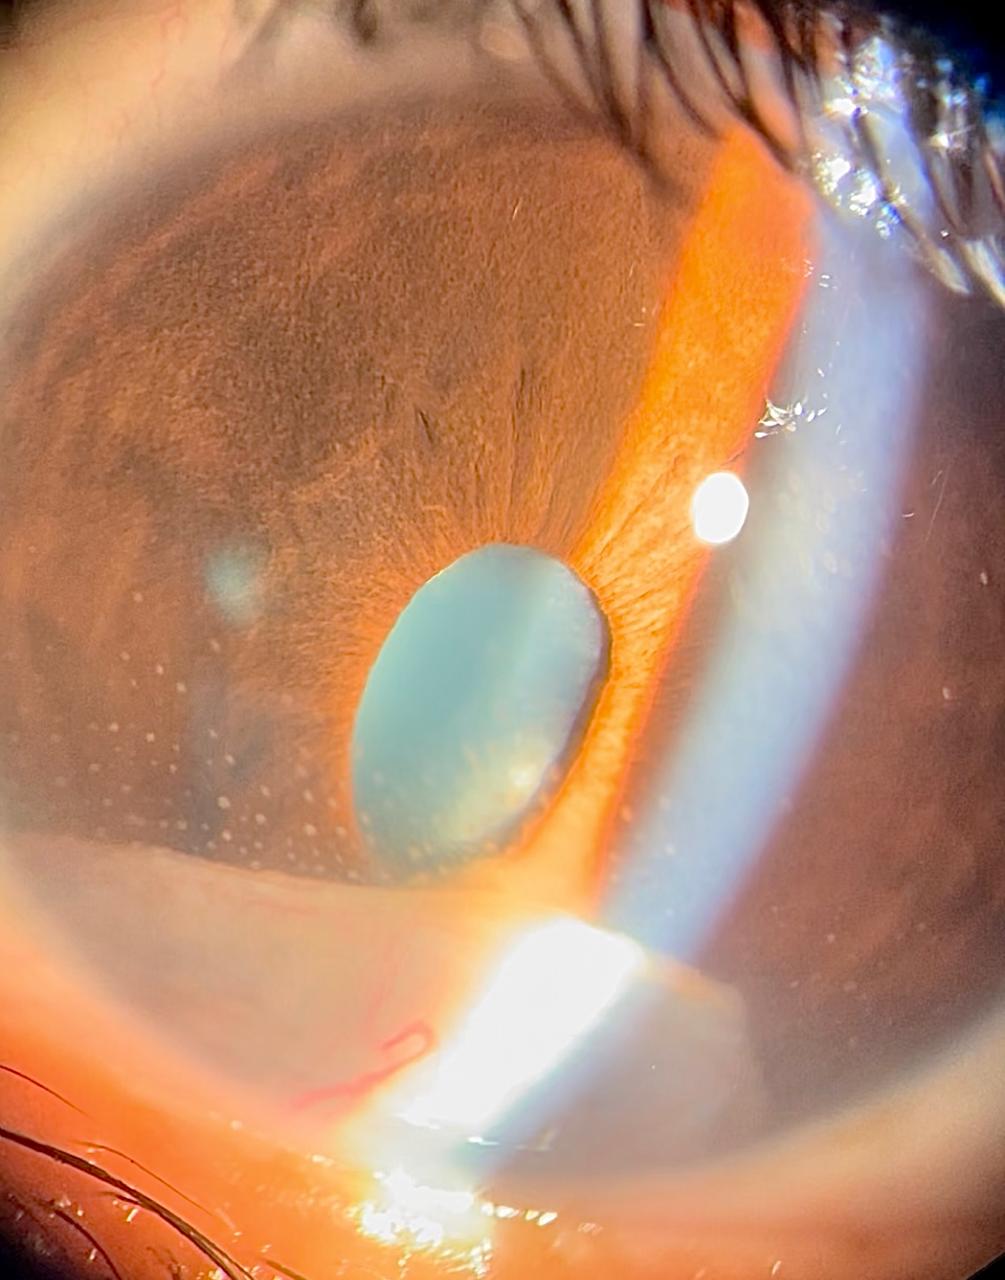

Figure 9 showing large, vascularised active retrocorneal membranous granuloma with adjacent granulomatous keratic precipitates and narrow peaked pupil due to strong adhesion of the membrane to iris surface

| current | 15:49, July 9, 2025 | 1,005 × 1,280 (105 KB) | Rana.Amin (talk | contribs) | Figure 9 showing large, vascularised active retrocorneal membranous granuloma with adjacent granulomatous keratic precipitates and narrow peaked pupil due to strong adhesion of the membrane to iris surface |